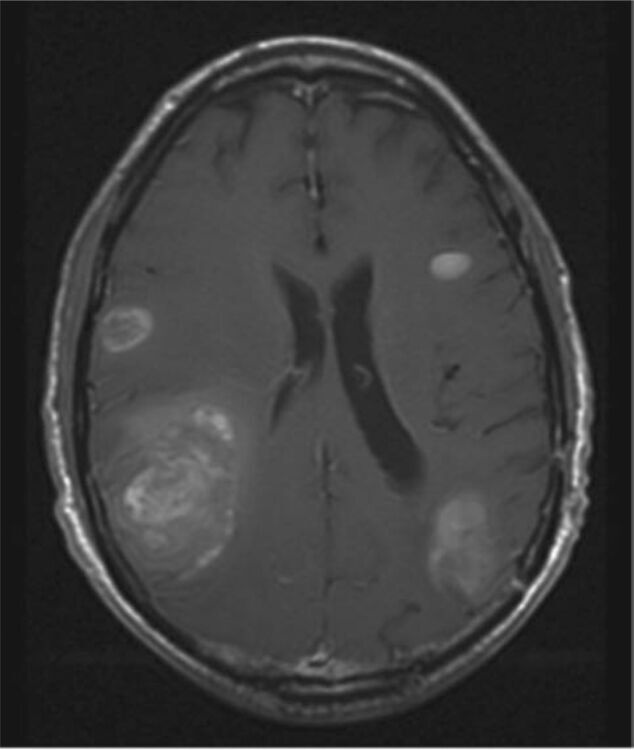

Join us every Thursday at 8 AM for a unique and informative Zoom event where medical experts gather to conduct a Brain Metastasis Tumor Board. During this virtual gathering, doctors will meticulously review complex patient cases, sharing their insights and knowledge on the latest advancements in brain metastasis treatment.

This interactive event is a valuable opportunity to witness the collaboration of top multi-disciplinary medical professionals as they discuss challenging cases and explore innovative solutions. To participate, registration for the event is required. Don't miss out on this weekly insight into the world of brain metastasis treatment and research!